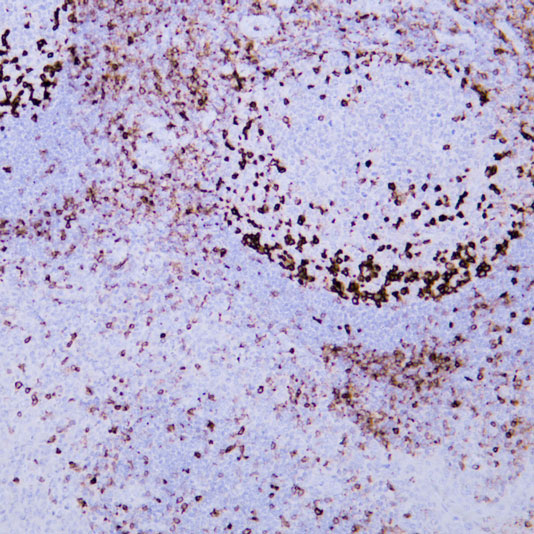

CD45 staining of paraffin-embedded human lymph node sections: Due to insufficient tissue fixation, lymphocytes at the edge of the lymph node show strong CD45 positivity, while those in the inner part of the tissue exhibit weak positivity, leading to uneven staining overall.

Lysozyme staining of paraffin-embedded human tonsil tissue sections showed non-specific staining due to edge effect (indicated by black arrows).